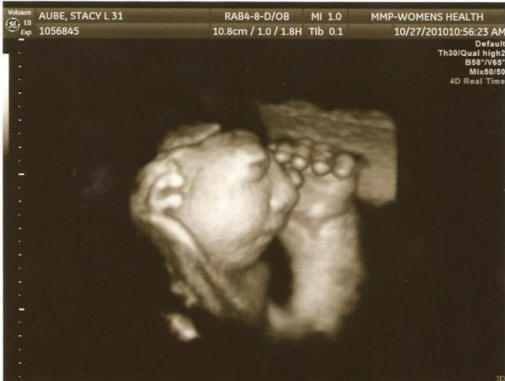

Снимки от открити източници, участващи в разследването експерти преодоляха медицинската документация на бременни от 27 области, регистрирани в антенатални клиники, изучаващи къде те работеха, отколкото бяха болни, пиеха ли алкохол, наркотици или пушени продукти, в кой район са живели и от какво източникът пиеше вода. В крайна сметка, държавни служители заключи, че не са в състояние да разберат „условията или причините“ на това явление. „Резултатите бяха разочароващи, но не съвсем неочаквано, призна ученият Джим Куцик (Джим Куцик), който участва в проучването. – Обикновено такива вродени дефекти причиняват комбинация от фактори, която е много трудна за откриване. не възможно е всичко това да е просто съвпадение. ” И тук е генетичното консултантката Сузи Бал смята, че в три окръга Щат Вашингтон има някакъв проблем, който трябва да се даде по-голямо внимание, за да се защитят жените в бъдеще на детеродна възраст. Внимание, шокираща снимка.

Снимка от отворени източници “Не бих искал да плаша хората, но това, което се случва, ме тревожи “, подчерта тя. – Получено от информацията за медицинския персонал трябва да бъде широко оповестена, че жените в детеродна възраст предприемат всички необходими мерки за предотвратяват развитието на тази патология. Като за начало ги съветвам приемайте фолиева киселина. ” Учените вече са прочели резултатите предишни проучвания, идентифициращи потенциални фактори риск от развитие на аненцефалия: ниско хранителен фолат киселини, излагане на пестициди и замърсяване на питейната вода нитрати.